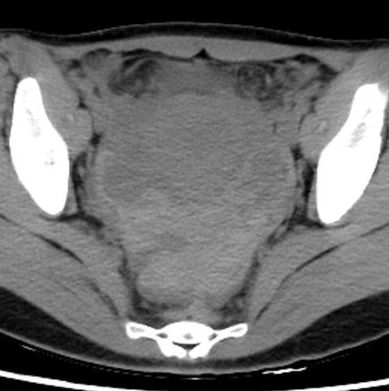

异位妊娠(宫外孕破裂)影像表现

女,24岁,因“停经42天,下腹痛3小时​”入院